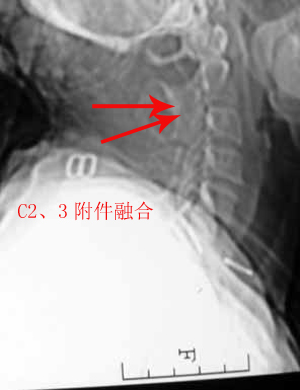

以下是引用zhangzhongshou在2007-4-29 22:53:00的发言:[br]1、c5半脱位,i度前滑脱。[br]2、c5椎板骨折。[br]3、第7幅图像显示右侧椎板骨折,哪一节颈椎,楼主自己知道。[br]4、c2、3附件融合畸形。[br]5、考虑环椎后桥,亦为正常变异。